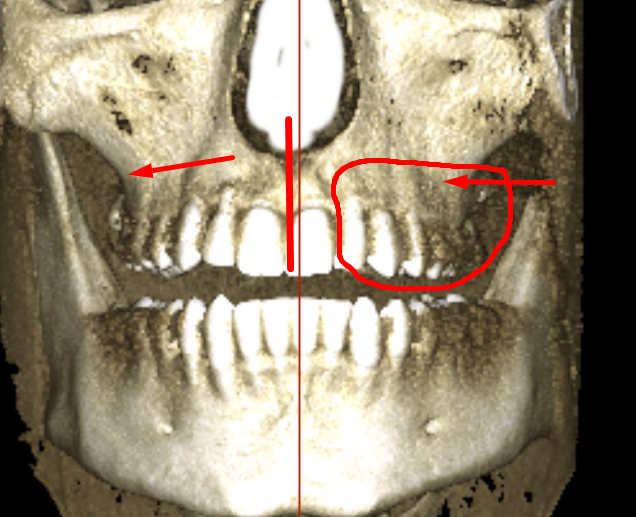

The chin is actually in line with the center of the skull

This is how it looks when i try ( and fail) to edit the midline towards center of the face

Isnt chin still centered or am i tripping?

seems to be centered, it's just the alveolar bone playing tricks with you head, your teeth are a lil overcrowded and the "midline" in the teeth has "shifted" (thankfully because of the xray you can see that with braces a clear aligner or even a toothborne expander you could fix your overcrowded lower teeth and move the "mid-line" to the right spot, your occlusion doesn't follow the "guide lines" of the bones also I notice that the upper jaw seems to be inlign with the "midline"(teeth and the base of the nasal cavity as you can see in the image)